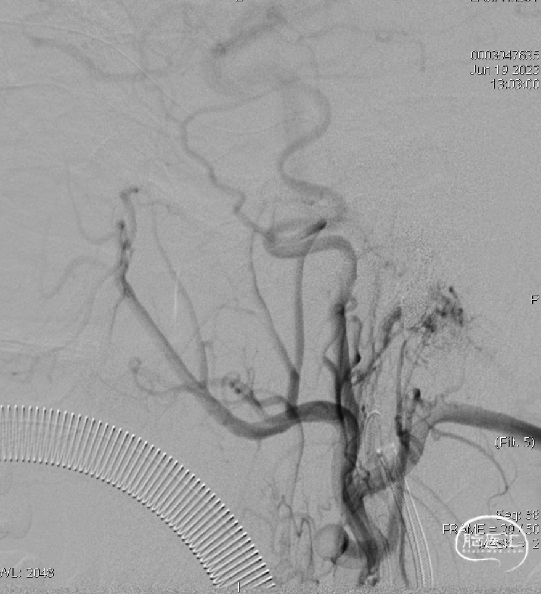

术后造影见瘘口不显影。

术后右侧颈总造影,未见向瘘口供血。

术后铸胶形态及CT下铸胶位置,可见瘘口位于左侧舌下神经管区域。